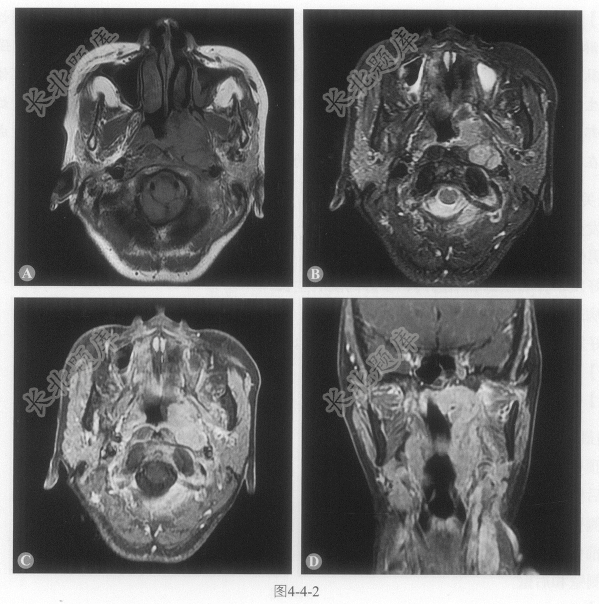

多项选择题1.患者的影像学表现包括:

A、鼻咽左侧壁及顶后壁明显增厚形成不规则软组织样信号肿物

B、鼻咽右侧壁未见明确肿物

C、T呈等信号,T2呈稍高信号,增强扫描明显强化

D、侵犯左侧腭帆张肌、腭帆提肌、左侧翼内肌

E、双侧咽后外侧组淋巴结肿大